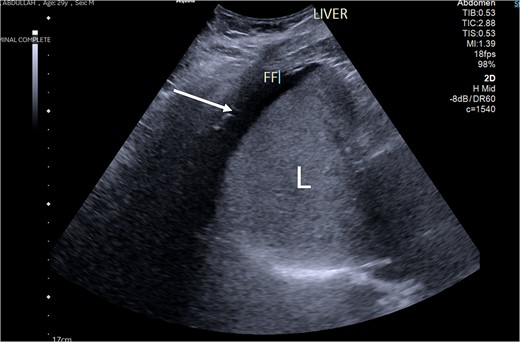

Patient was admitted, and his laboratory investigations demonstrated a normal CBC level, electrolytes were also within normal level, total bilirubin: 17.10 μmol/L, direct bilirubin: 8.80 μmol/L, amino transferase alanine: 36.00 u/L, amino transferase aspartate: 19.00 u/L, alkaline phosphatase: 83 0.00 u/L. Abdomen ultrasound demonstrated mild to moderate intraperitoneal fluid collection, noted mainly in the perihepatic, peri splenic region (Fig. 1). Computed tomography (CT) with oral and IV contrast was ordered for further assessment. The CT showed a non-enhancing portal vein and its branches, a superior mesenteric vein and its tributaries, which are engorged and associated with dirty and congested mesentery, as well as a small amount of peritoneal free fluid denoting venous thrombosis along the portal mesenteric axis with no evidence of contrast leak from the gastric sleeve (Fig. 2). Vascular surgery and hematology consultations were immediately done; they assessed the patient and started him on enoxaparin 100 mg along with a serial abdominal exam. On Day 2 of the current admission, the patient had one episode of fresh blood per rectum, around 150 ml of fresh blood, and dark blood-tinged vomiting of minimal quantity around 10 ml. The patient became agitated, and his abdomen was distended with generalized tenderness. He was immediately resuscitated with two unmatched red blood cell pack transfusions, and then shifted to intensive care units. CT scan angiography of the abdomen was done at that time and reported as follows: non-enhancing portal vein and its branches, superior mesenteric vein and its tributaries, which are engorged and associated with dirty and congested mesentery with a slight increase in the amount of peritoneal free fluid denting venous thrombosis along the portal mesenteric axis. Mild diffuse mural wall thickening of the small bowel is likely related to venous congestion. Aorto-iliac arteries: the visualized abdominal aorta and its bifurcation into right and left common iliac arteries appear intact. The common iliac arteries, internal and external iliac arteries appear intact bilaterally. Mesenteric arteries: the main trunk of the superior mesenteric artery appears intact with no obvious segmental arterial stenosis or occlusion. The inferior mesenteric artery and its main divisions appear intact, with no obvious main or branch occlusion. Celiac artery: The celiac artery and its main divisions, including hepatic, gastric, and splenic divisions, appear intact with no obvious main or branch occlusion.

An ultrasound picture showing free fluid (FF) (white arrow) around the liver (L).